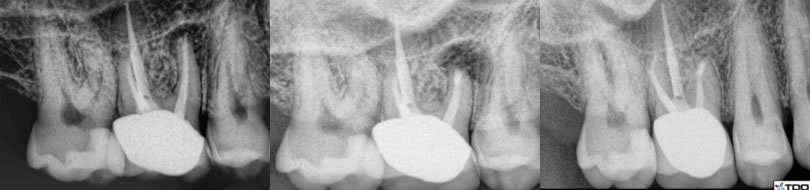

4. Severe canal transportation by original root canal therapy that would make retreatment impossible. (figures 12,13,14)

Figures 12,13,14: pre-op / post-op / 6 month recall

In this case there was a transported canal in combination with a large post. Therefore, surgery made a lot of sense rather than full dis-assembly of the crown/post complex with potentially very limited upside on the retreatment. I performed conventional treatment on #14 and apicoectomy on #13 and the healing looks great after just 6 months.

5. Separate instruments that would prevent retreatment endodontics. (figures 15,16,17,18)

Figures 15,16,17,18: pre-op / post-op retreatment / post-op apicoectomy / 13 month recall

I performed retreatment endodontics first with hope of bypassing/removing the separated instruments in the mesial canals. I was only able to retreat the distal canal and then performed apicoectomy on the mesial canals. He has been asymptomatic and comfortable since treatment.